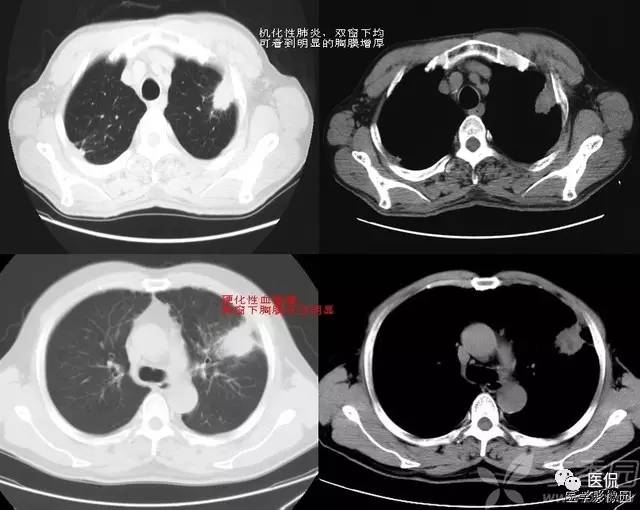

胸膜凹陷征(PI)

胸膜凹陷征(PI)也称为“兔耳征”、“尾征”或“胸膜尾征”。PI为肺癌侵达胸膜的最直接的影像学证据,一直以来普遍认为是肺恶性肿瘤的典型征象。胸膜凹陷通常以肺脏肋面最多,其次为纵隔面、叶间胸膜面、膈面的脏层胸膜或胸膜多处受累。典型PI对周围型肺癌有重要诊断价值。有日本学者研究认为,PI阳性较PI阴性的周围型肺癌病人5年生存率明显降低。目前认为形成典型PI的主要病理基础是肿瘤方向的牵拉而局部脏壁胸膜无增厚粘连。肿瘤牵拉的原始力量来自于瘤体内反应性纤维化及瘢痕形成,收缩力通过肺的纤维支架结构传导到游离的脏层胸膜而引起凹陷。肺癌的胸膜凹陷形成多是由于瘤内有纤维瘢痕,引起肺外周支架结构收缩移位,牵拉胸膜形成凹陷,这种病理变化在一定程度上也形成了肿瘤的分叶切迹。肺癌牵拉胸膜内陷的动力主要由肺癌本身纤维增生、肺癌周围肺组织的纤维增生和肿瘤阻塞小支气管引起的肺不张产生,但PI的形成还应基于局部胸膜不粘连这一基础,同时还有其他因素在起作用,如肺癌到胸壁的距离。PI的典型CT表现为肿瘤远端与胸壁间线状影加小三角形影或喇叭口影,三角形基底位于胸壁缘,尖指向肺内包块。三角形影或喇叭口影与壁层胸膜间被水充填。喇叭口周围胸膜无增厚亦无粘连,这种改变国内学者称为“典型PI”,以肺癌多见。

文献将PI线状影是否与肺内病灶棘突相连或深达病灶边缘并该处肿瘤凹陷,作为肺外周良、恶性结节或包块的另一项重要鉴别诊断指标。NNPI是指胸膜线影进入结节内部,于结节表面形成切迹改变。此征对恶性胸膜凹陷诊断特异度为96.5%。外周肺炎性病变通常伴胸膜增厚、粘连,并非单纯脏层胸膜凹陷所引起。胸膜明显增厚者常无明显胸膜凹陷或虽有凹陷但较浅而不规则,称“不典型PI”,以炎性病灶多见。就炎性病变而言,不典型PI的形成可能与胸膜的粘连关系大。外周肺炎性病变尤其是结核较易累及胸膜,引起渗出,纤维蛋白沉积,吸收过程中造成胸膜的粘连、增厚。文献普遍认为,肺良性病变PI的MSCT表现,PI伴胸膜增厚粘连,造成所见线状影粗细不均,故在CT上缺乏完整PI的变化规律及胸膜面三角形影,是鉴别肺癌PI的关键。也有研究显示,肺外周良性病变PI多表现为以下两种情况:棘状胸膜凹陷,肺内病变与胸膜间见粗线状、索条状或棘状高密度影伴胸膜牵拉内陷;幕状或宽基底胸膜凹陷,病变胸膜侧一定范围与胸膜粘连相贴,形成盘底征,并伴有相应区域胸膜粘连增厚。文献报道叶间胸膜凹陷多见于周围型肺癌,但也有研究显示肺外周良、恶性结节或包块,叶间胸膜凹陷所占比例相近,并无明显差别。

总之,PI多见于周围型肺癌,其中又以腺癌最为多见,该征象亦可见于肺良性病变,如结核球、慢性炎症、炎性假瘤、肺脓肿、硬化性血管瘤等。其中Ⅰ、Ⅲ、Ⅴ型PI多见于周围型肺癌,而Ⅱ、Ⅳ型PI则在结核球等良性病变中多见。即便如此,各种形态PI在肺外周良、恶性病变的CT图像上有重叠,并无绝对的特异性。将该征象与肺外周结节的毛刺、分叶、支气管血管聚集征等其他主要征象以及临床资料进行综合分析,可提高肺外周结节的CT诊断准确率。

附:PI的分型

I型为典型表现:结节与脏层胸膜面间约1mm粗细的一根或一组呈放射状排列指向病灶中心(或肺门)的线条状影,伴或不伴脏层胸膜小三角形或喇叭口形影,无胸膜增厚;II型:有I型表现,轻或无脏层胸膜凹陷,有胸膜增厚(厚度>2mm);Ⅲ型:结节与脏层胸膜面间呈梳齿状排列的线状影,常有胸膜增厚;IV型:病灶位置太高或太低,PI中心呈上下斜形走行,CT横断像不能显示完整的PI,表现为多个层面显示结节与脏层胸膜间在肺门一结节中心连线方向上点状或线段影,脏层胸膜可见“U”形影;V型:为叶间胸膜凹陷,表现为叶间胸膜纤维牵拉向结节侧弧形移位或走行失去连续性。

从形态上讲,胸膜凹陷症又分为:1)线型;2)幕状粘连;3)锥型;4)星型四个类型。